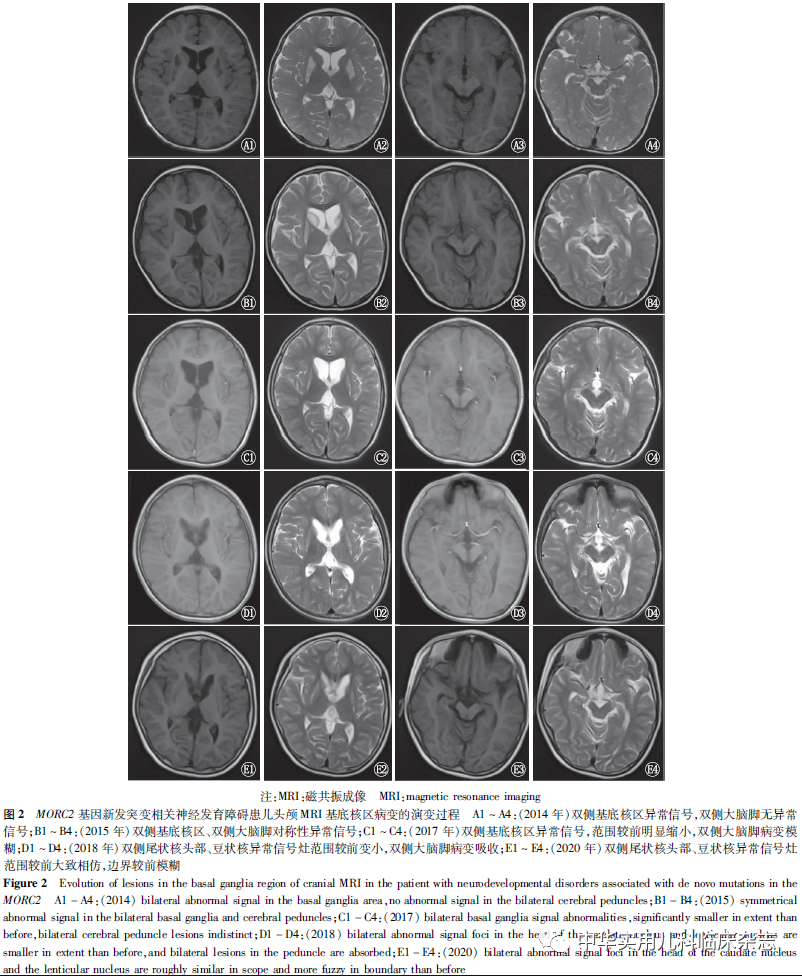

临床资料回顾性分析。患儿,男,7岁,因发育迟缓于2020年7月就诊于福建医科大学附属协和医院门诊。患儿系第1胎,第1产,足月剖宫产出生,出生体质量3 kg,出生过程顺利,无窒息抢救史,出生6个月时发现发育落后于同龄儿童,1岁会坐,1岁8个月会爬,2岁时会走数步,1岁时会有意识的叫“爸爸妈妈”,但进步缓慢。1岁7个月时,开始予康复训练,进步缓慢;2岁8个月时因“上呼吸道感染”发热1 d后出现嗜睡、运动倒退、独走不稳、不能说话,经治疗后运动恢复到独走数步,能听懂指令,无语言。2岁10个月时,诊断“线粒体病(Leigh综合征)、痉挛性瘫痪(下肢)、营养不良”,予 “鸡尾酒”疗法、补充维生素D、生物素、营养支持及巴氯芬等治疗,患儿运动及智能逐渐改善。现7岁,可独立行走,会表达需求,会说短语,已停用所有治疗药物1年。查体:身高112 cm(-2.06 SD),体质量22.9 kg(0 SD), 头围 49 cm(-1.91 SD),神志清楚,精神可,鼻梁高耸,上唇薄、牙齿稀疏、腭弓高(图1),心肺腹未见明显异常,痉挛步态,双上肢肌力正常,双下肢肌力4级,双下肢肌张力增高,双侧腱反射活跃,双侧踝阵挛阳性,双侧巴氏征阳性。辅助检查:(2014年8月)血检提示代谢性酸中毒、乳酸升高(4.23 mmol/L),血尿遗传代谢筛查未见明显异常;(2015年11月)维生素D 18.1 μg/L,生物素74.95 ng/L,生物素酶179.08%;(2016年8月)溶酶贮积症酶学分析正常;(2020年8月)复查血乳酸正常(2.6 mmol/L)。(2014年8月)肌电图:未见明显异常。头颅磁共振成像(MRI)影像学变化过程见图2。6岁时行小儿神经心理发育评估(发育商):总发育商:26.0,大运动:15.0,精细动作:27.0,适应性:25.5,语言能力:16.5,社交行为:16.5。染色体微阵列及线粒体病相关基因检查均未见明显异常。外显子测序显示:MORC2基因突变,chr22:31345763,NM_001303256.3:c.292G>A(p.Gly98Arg),新发杂合突变,父母均为野生型(图3),美国医学遗传学与基因组学学会(ACMG)指南[9]评级为可能致病(PS2+PM2)。UCSF Chimera软件预测蛋白质结构改变(图4),PolyPhen-2和SIFT预测该蛋白改变为可能具有破坏性和有害的。本研究患儿监护人均知情同意,并签署知情同意书,并通过福建医科大学附属协和医院医学伦理委员会批准(批准文号:2021KY007)。

讨论本研究报道了1例MORC2基因新发突变相关的神经发育障碍性疾病,其主要表现为婴儿期起病的全面发育落后,身材矮小、头围小,伴头颅影像学类似Leigh综合征改变。全外显子测序显示其MORC2基因5号外显子发生一处新发杂合错义突变[c.292G>A(p.Gly98Arg)],该突变尚未被报道过,根据ACMG指南[9]分级,该突变为可能致病。MORC2基因新发突变相关的神经发育障碍性疾病是一种刚刚被发现的综合征,目前仅有20例病例报道[8],尚未见中国人群该综合征的相关报道。MORC2基因位于染色体22q12.2(chr22:31,321,117-31,364,284),含有26个外显子[10],MORC2基因编码一种依赖于DNA的ATP酶,它是通过染色质修饰实现表观遗传沉默的ATP酶家族的一员,在染色质重塑、DNA修复和转录调控中发挥作用[8]。MORC2基因突变与人类神经系统的疾病相关性2012年才被注意到[11],它参与表观遗传沉默并在发育早期的神经组织中表达,也能结合ATP柠檬酸裂解酶,该酶催化形成的乙酰辅酶A是多种生物合成途径的关键组成部分,这可能是其导致神经发育障碍的潜在机制[12-13]。既往研究认为,MORC2基因突变主要与常染色体显性遗传的CMT-2Z型有关[14-17]。其与神经发育障碍的关系并未受到重视。Guillen Sacoto等[8]综合分析了20例表型相似的患者队列,这些个体均在MORC2的ATP酶模块中携带致病性突变,其中MORC2突变导致了由沉默复合体引起的表观遗传沉默的过度激活。通过对其详细的表型信息以及遗传学信息的分析,作者定义了一种新的综合征,其特征是全面发育迟缓、身材矮小、小头畸形和多种面部畸形,伴或不伴神经病变,部分患者头颅影像学改变类似Leigh综合征。在这20例患者中,15例患者为新发杂合突变,本研究发现的患者亦为新发杂合突变,提示新发突变可能是该综合征主要的基因突变形式,其遗传方式为常染色体显性遗传。结合既往报道及本研究的发现,该综合征相关的MORC2基因突变均为错义突变,且都位于外显子上,其分别分布于2、5、6、9、13、14号外显子,其中突变位于2号外显子的最多(6例,28.6%);c.79G>A(p.Glu27Lys)突变最为多见(5例,23.8%),其是否可能为热点突变,有待将来的数据进一步证实。所有氨基酸突变均位于ATP酶模块上,其中类Leigh综合征改变的患者其氨基酸突变均位于ATP酶模块中的GHKL型ATP酶结合域内,20例患者中氨基酸突变不在该区域的均未出现类似Leigh综合征的影像改变,而氨基酸突变位于在该区域的患者41.6%出现了类似Leigh综合征的影像学表现,提示MORC2基因突变导致的氨基酸突变如果位于GHKL型ATP酶结合域内,其头颅影像学可能出现类似Leigh综合征的改变,其相关机制尚不清楚,对于此类突变的患者,应密切关注其头颅MRI的变化,同时需注意与Leigh综合征鉴别。20例患者中,10例患者进行了周围神经病变的评估,其中6例患者伴有周围神经病变,其基因型分别为c.260C>T(p.Ser87Leu)(2例)、c.394C>T(p.Arg132Cys)(2例)、c.1181A>G(p.Tyr394Cys)(2例)。其中p.Ser87Leu是CMT2Z最常见的突变之一[12],而p.Arg132Cys及p.Tyr394Cys未见报道与CMT2Z相关[18];CMT2Z另一个常见的突变为p.Pro252Try[12],20例患者均未发现该突变类型;提示对于MORC2基因突变相关的神经发育障碍的患者临床应注意评估有无周围神经病变,尤其是突变为p.Ser87Leu的患者。本研究发现的患者其基因突变为c.292G>A(p.Gly98Arg),尚未被报道过,其相应的氨基酸改变位于已报道可引起致病的GHKL型ATP酶结合域内,根据软件预测其能引起MORC2蛋白的空间结构发生改变,具有破坏性,为有害病变。目前尚未发现临床表型与基因型之间有特异性相关[8]。6例类Leigh综合征的患者年龄为4.2 ~7.0岁,男女各3例;均有语言、运动及智能的损害,智力障碍程度不等,严重者较多见;均有神经肌肉异常的表现,主要为肌力减弱、腱反射亢进、姿势步态异常,但仅1例患者肌电图提示感觉运动轴突神经病;头颅影像学病变主要位于基底核区。本研究报道的患者为目前已知的类Leigh综合征中的年龄最大者。患者病初多次查血浆乳酸高,亦有感染后病情加重的表现,头颅影像学表现为双侧基底核区的长T1长T2改变,符合Leigh综合征的临床诊断,予“鸡尾酒”疗法治疗,运动和智能均有改善,复查头颅MRI基底核病变也逐渐缩小,提示虽然MORC2相关神经发育障碍综合征具体作用机制尚不明确,但在临床治疗过程中可能可以尝试针对线粒体病的相关治疗方法,如“鸡尾酒”疗法,可能有效。与线粒体病中的Leigh综合征不同的是,该患儿虽然也是婴幼儿起病的全面发育落后,亦有一次感染后病情加重的过程,但其预后较线粒体病Leigh综合征明显要好,本例患儿随着年龄的增加,病情逐渐改善,且停用“鸡尾酒”疗法1年后临床观察其运动及智能仍在改善,复查血浆乳酸正常,头颅MRI提示颅内病变无加重。综上,本研究报道了首例中国人群的MORC2基因突变相关的神经发育障碍综合征,该综合征主要特征为:全面发育迟缓、身材矮小、小头畸形和各种畸形面容,可伴或不伴神经病变,其头颅影像学可类似Leigh综合征的改变,其基因突变均位于外显子上,且均为错义突变,以c.79G>A(p.Glu27Lys)突变最为多见,“鸡尾酒”疗法可能对其有效。